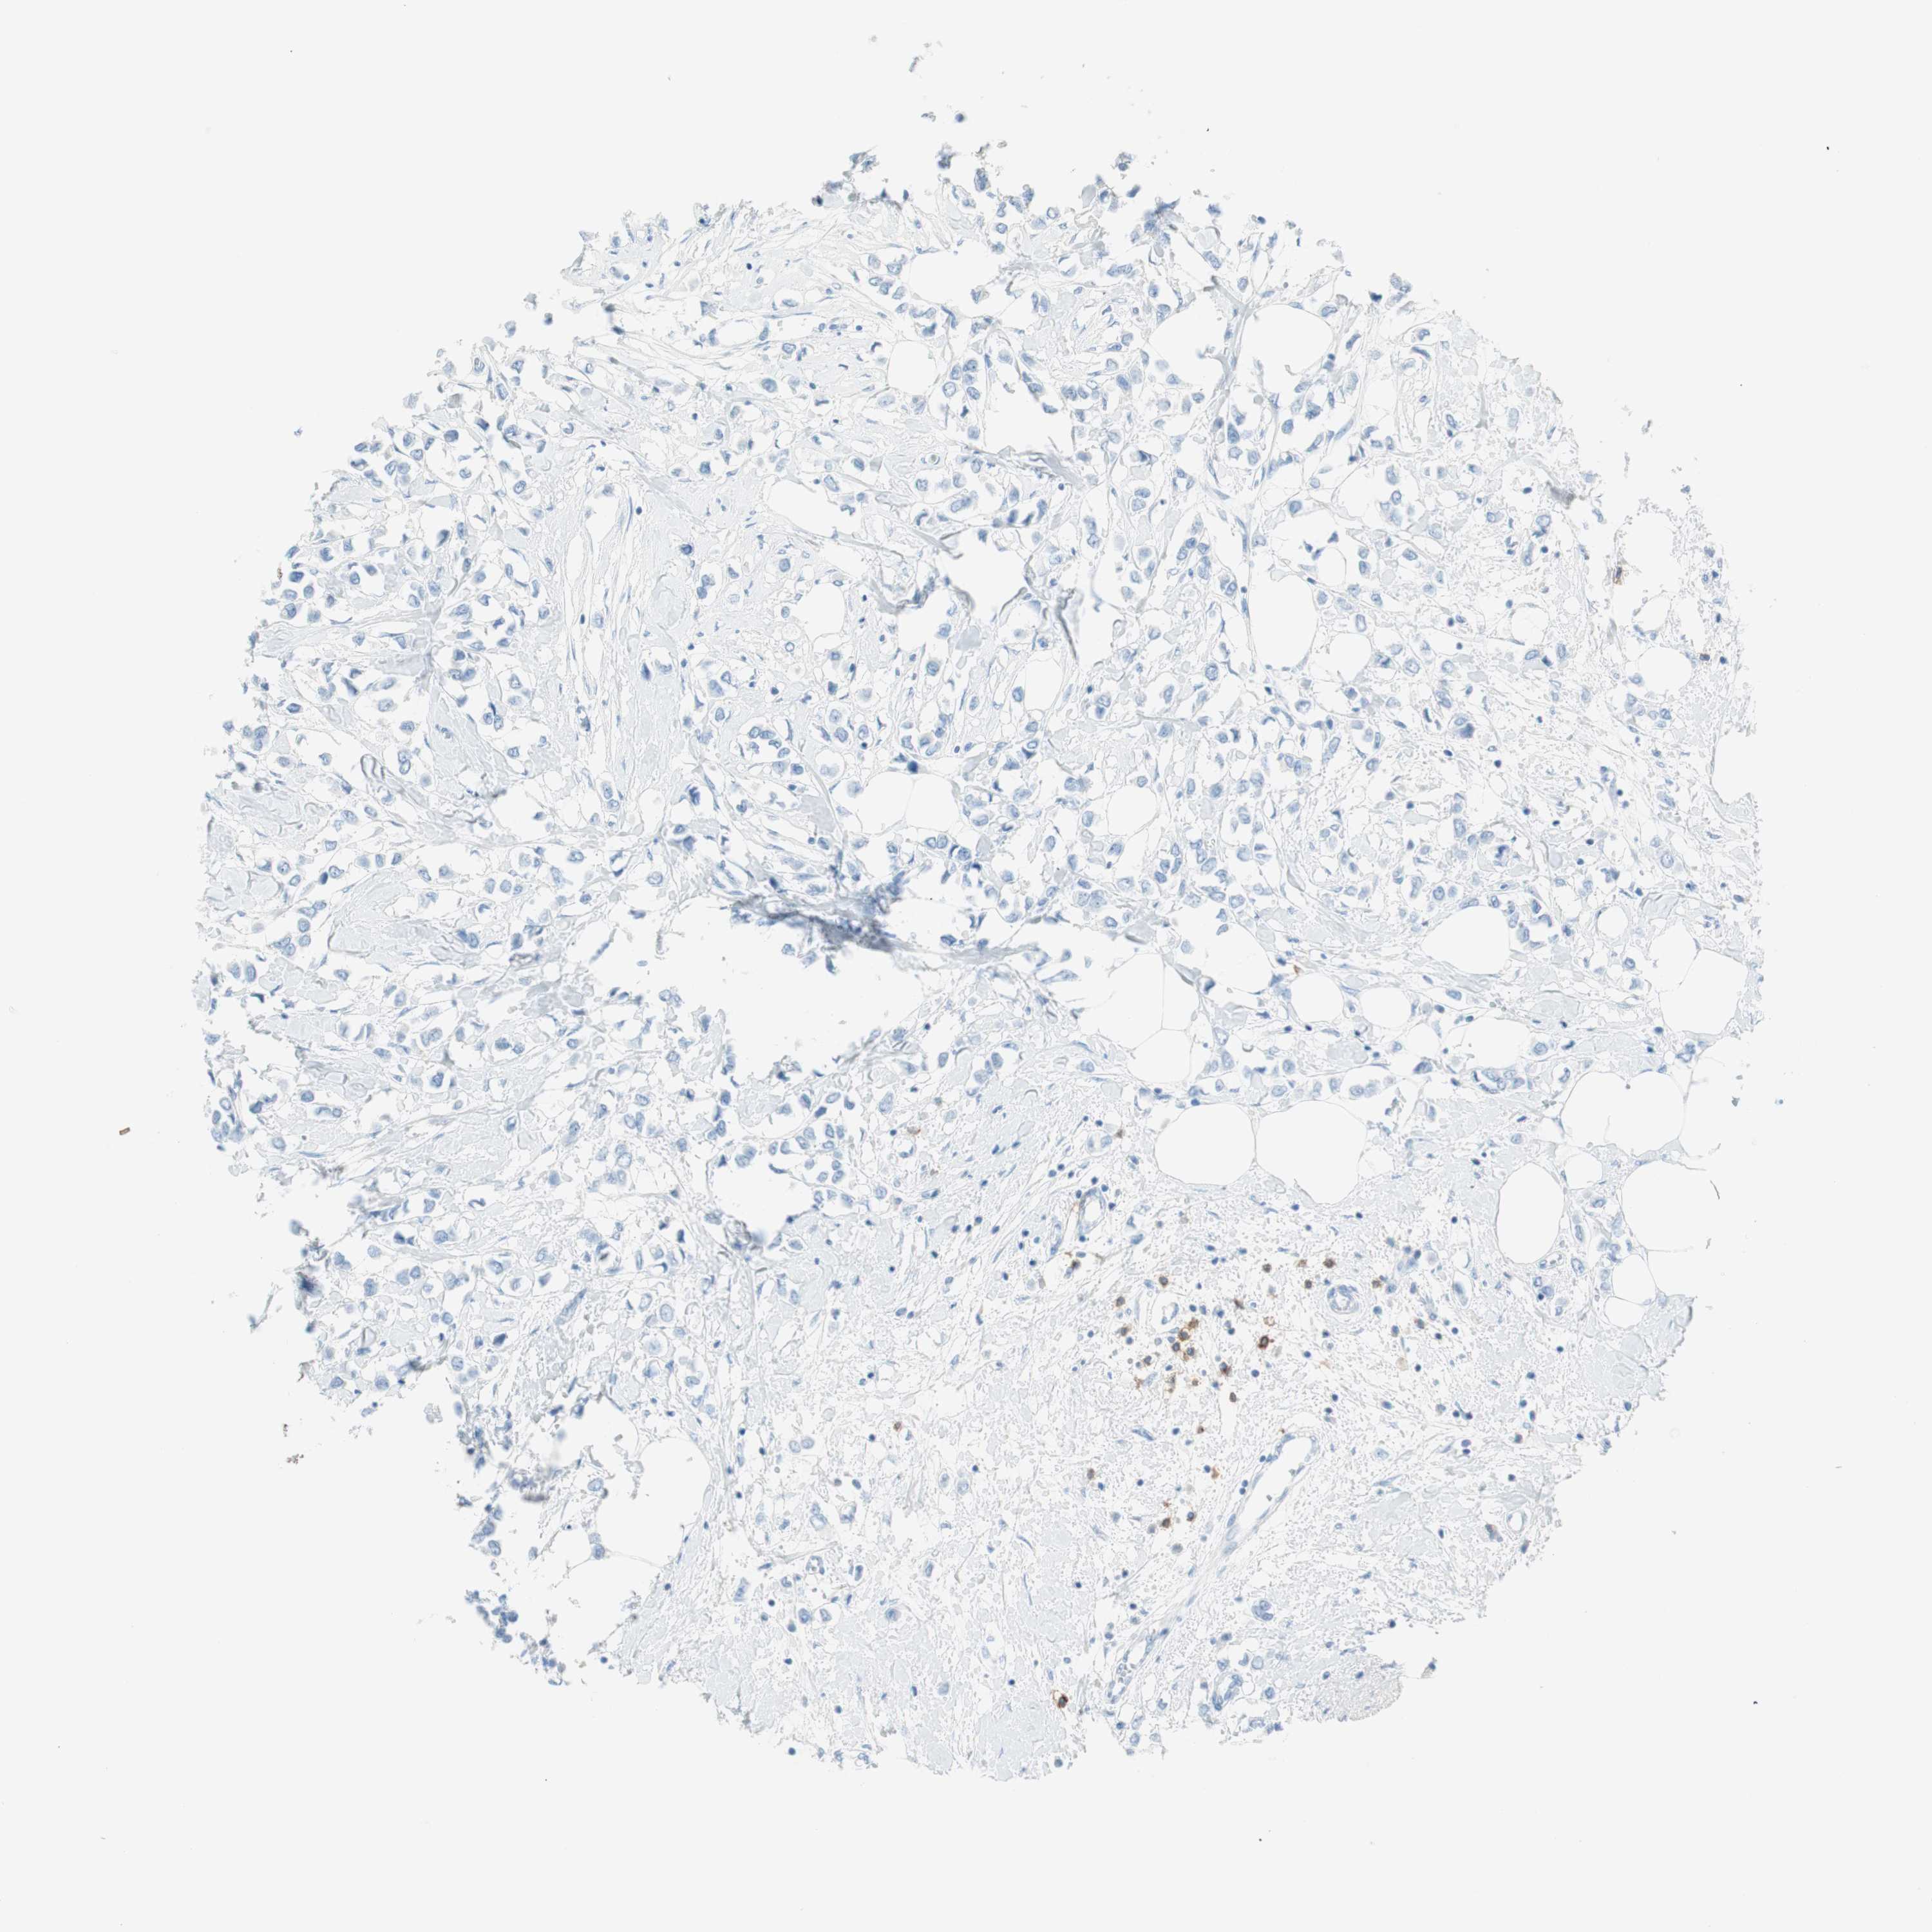

BRCA TCGA BRCA VALIDATION PROTEIN EXPRESSION

ANTIBODIES

AND

VALIDATION